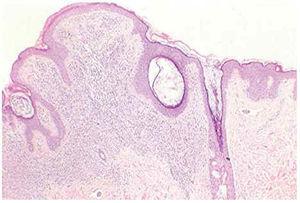

En los casos 5 y 6 no existían criterios concluyentes de nevo congénito. Los pacientes recordaban tener las lesiones pigmentadas desde hacía años, pero no desde la infancia. En el caso 5, la paciente tenía como antecedente un nevo displásico en otra localización. La lesión pigmentada incluida en el estudio correspondía a un nevo melanocítico intradérmico con componente lentiginoso suprayacente, con características diagnósticas de nevo compuesto. En ambos casos se observaron estructuras vasculares linfáticas en la dermis adyacente a la lesión, que contenían melanocitos en su luz en forma de agregados irregulares o adheridos al endotelio (figs. 4 y 5). Por último, el caso 8 (que correspondía a un nevo intradérmico común), presentaba masas polipoides de melanocitos que protruían en la luz de los vasos linfáticos situados en el seno de la proliferación melanocítica dérmica.

Fig. 5.--Detalle de los émbolos melanocíticos en la dermis adyacente. (Hematoxilina-eosina, ×100.)